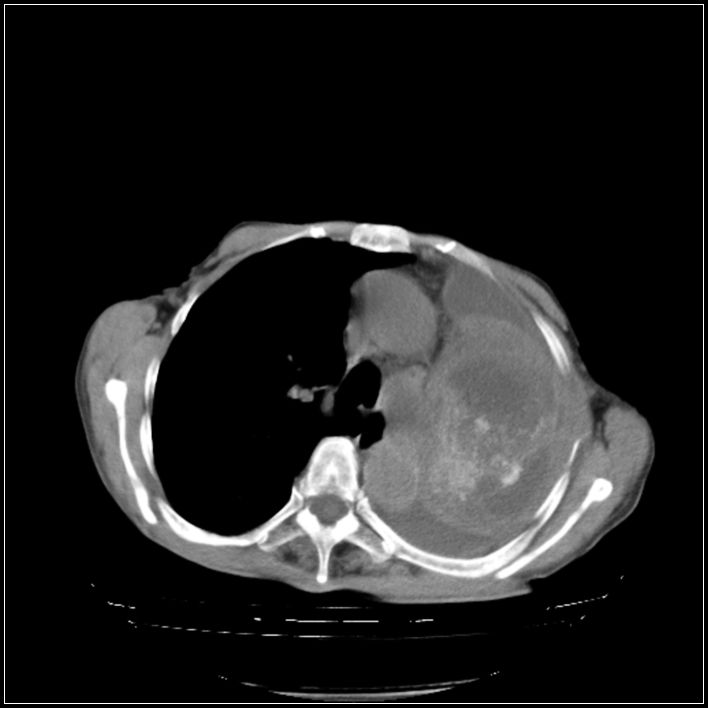

以下是引用ydx_74在2008-5-31 16:08:00的发言:[br]中心性肺癌并左侧肺不张、胸水。